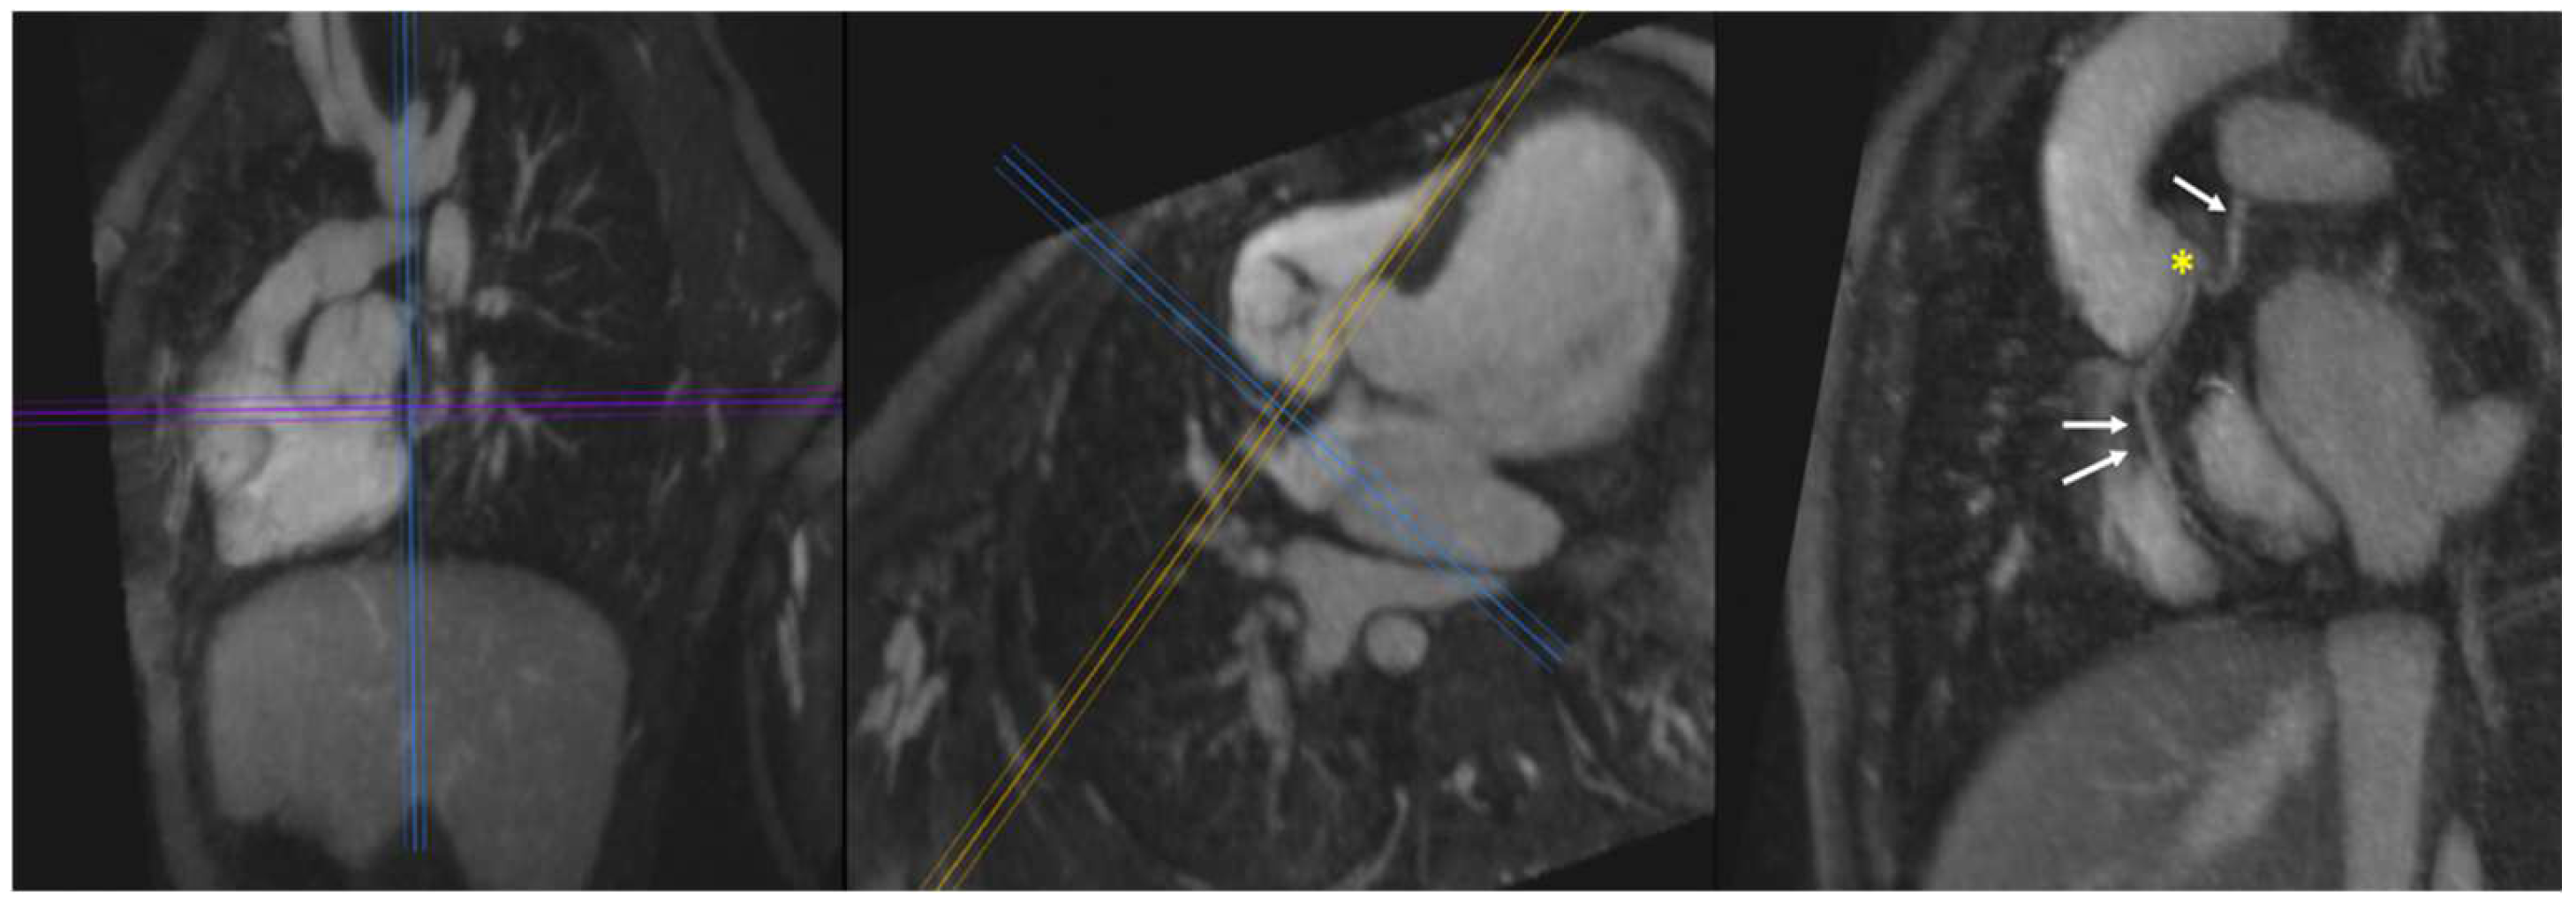

4.4. Intracardiac Anatomy

4.4.1. Unbalanced Atrioventricular Canal Defect

4.4.2. Hypoplastic Left Heart Complex

4.4.3. Coronary Artery Anatomy